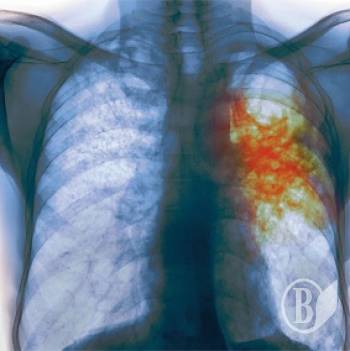

Одна из воспитательниц черниговского детсада №22 оказалась больной открытой формой туберкулеза.

«А в мае она оказалась больной открытой формой туберкулеза, хотя эта стадия длится от 6 до 10 месяцев. Врачи же на собрании заверяли, что она только что заболела», - пишет Виктория Пискун.